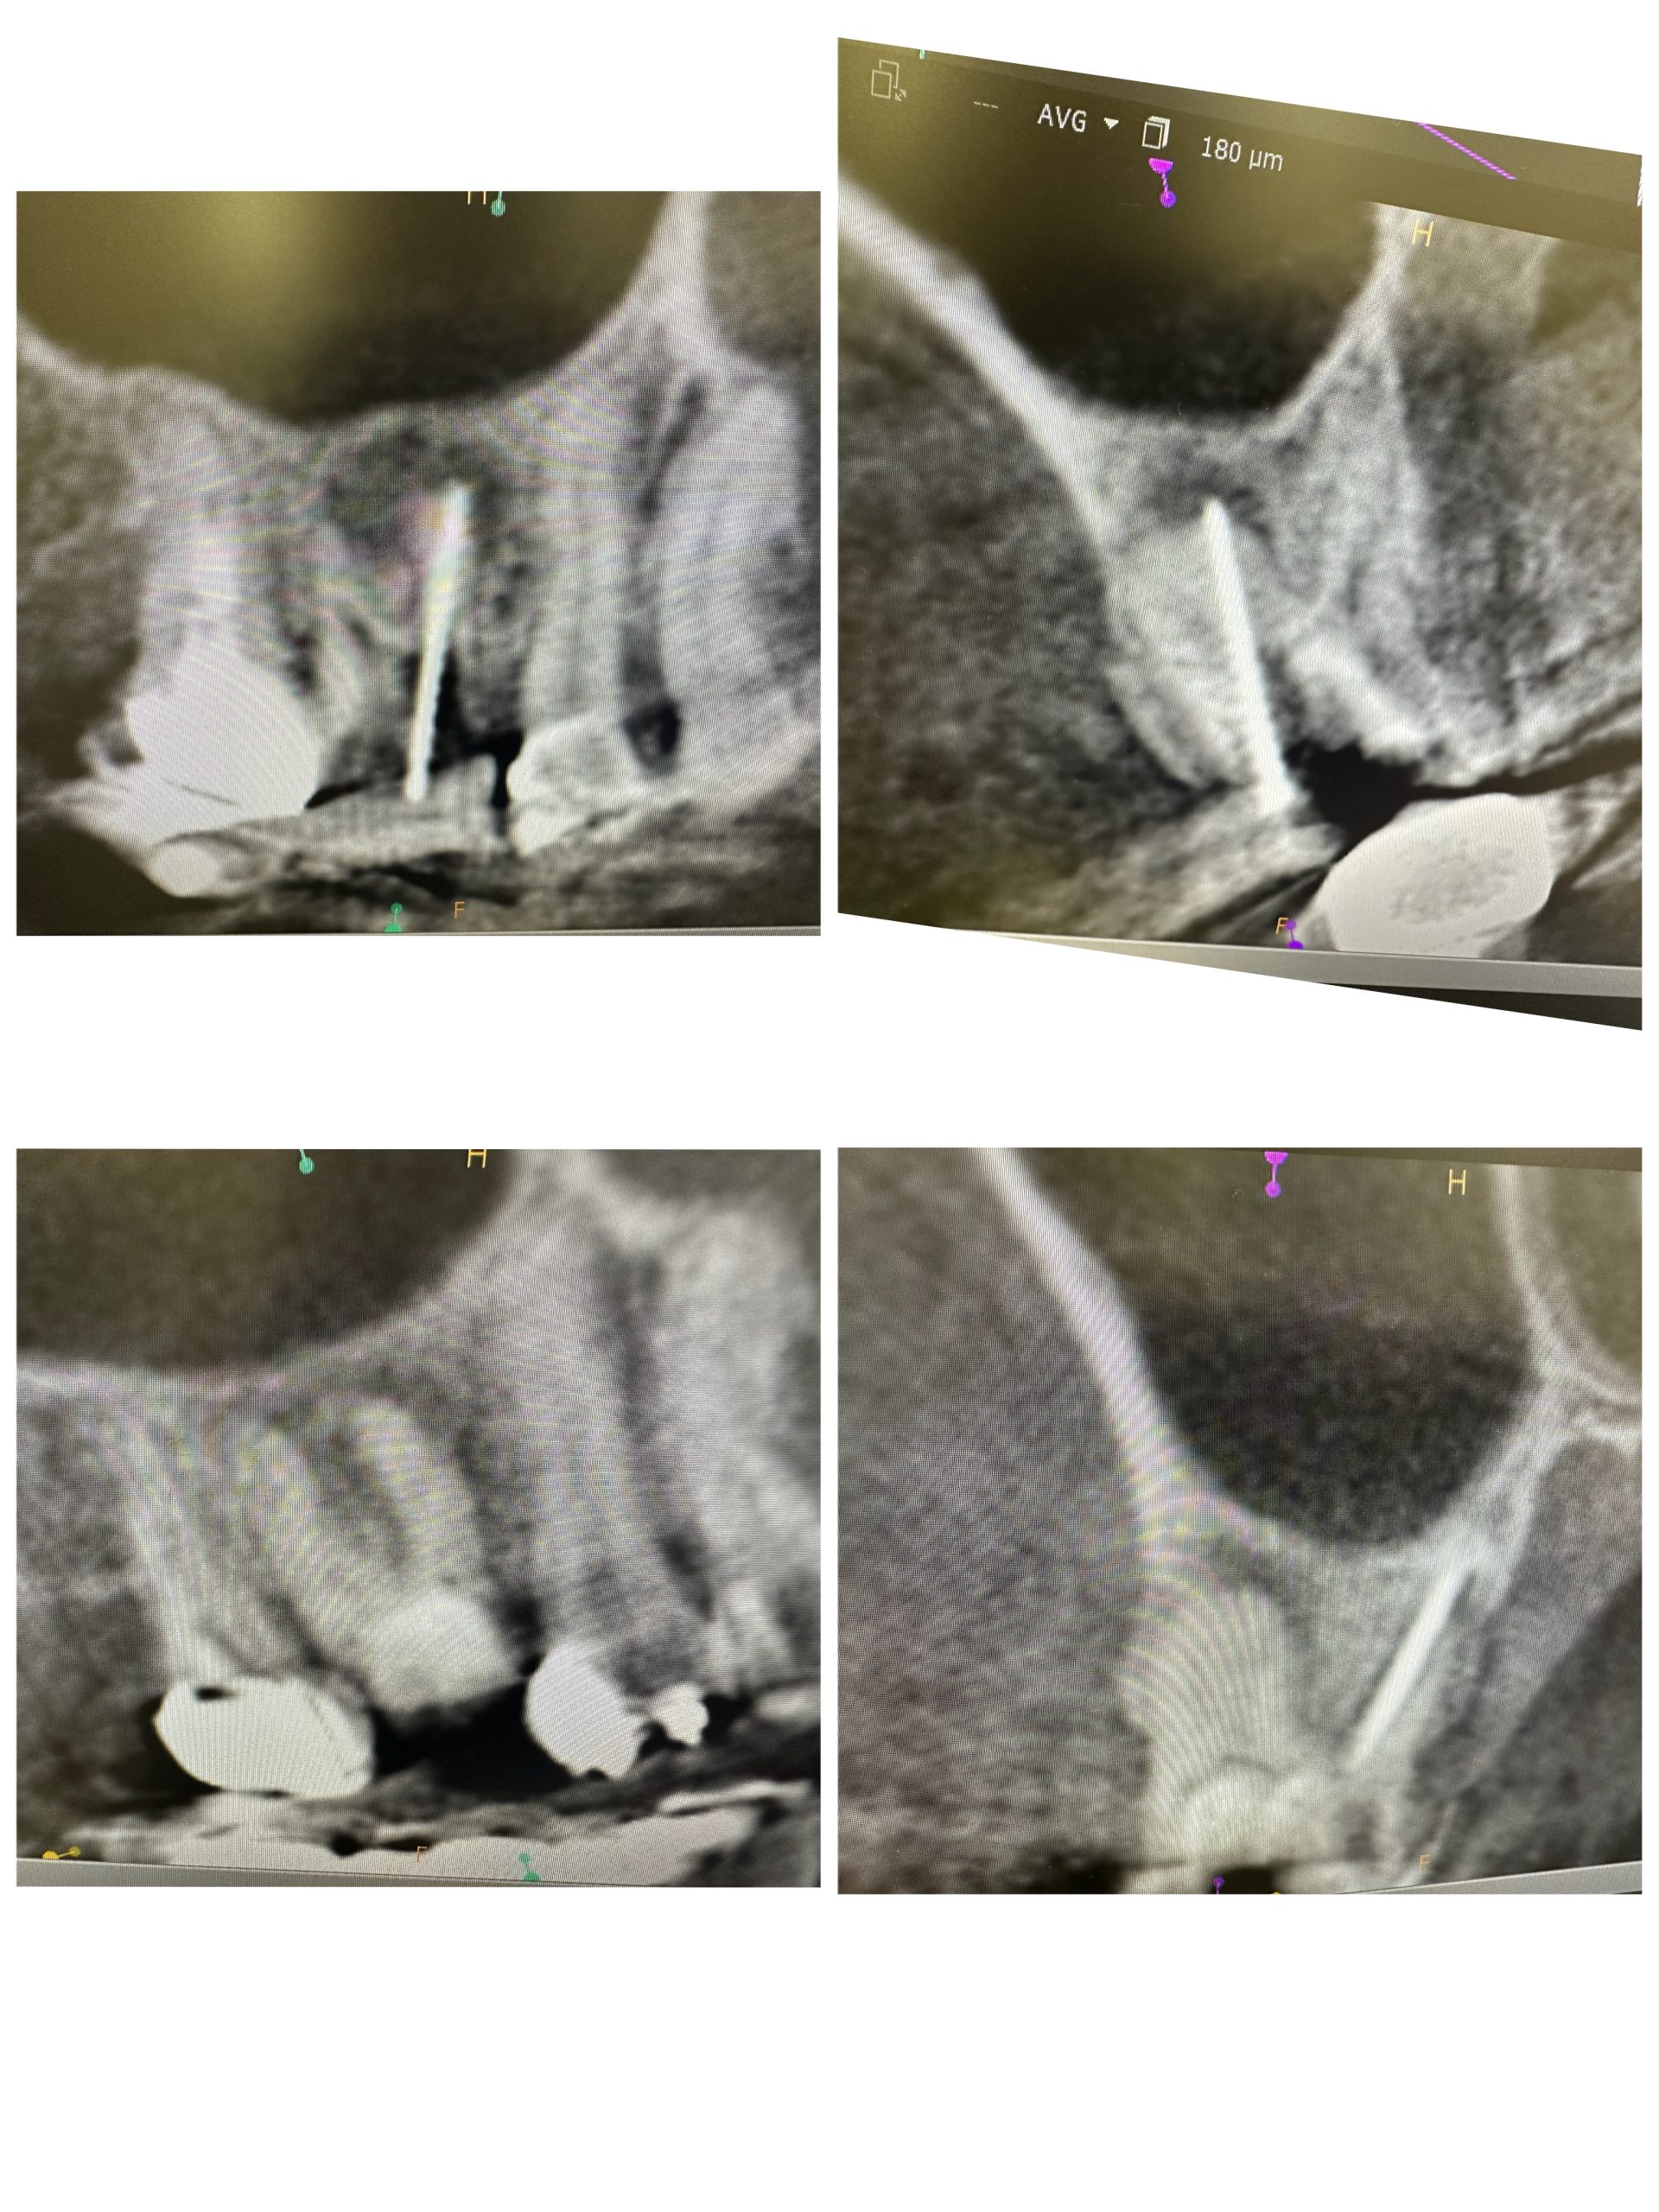

次は根管治療

意図的穿孔、60歳代、病巣が大きく、ファイルが全く開通せず

このような場合に使う手段の意図的穿孔

母校神奈川歯科大学の後輩長尾論文からアイデア得て、よく使わせてもらってます、薬剤が直接患部に作用するから治りも早い

これで3ヶ月経過、来月MTA根充予定